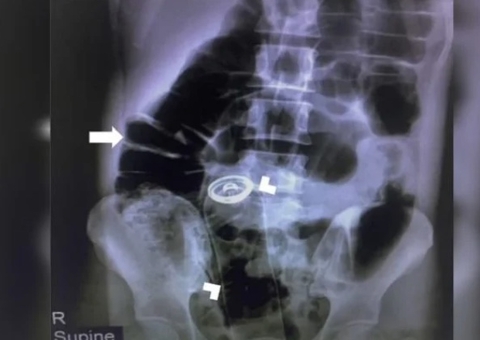

Um detento escondeu uma tesoura de 20 centímetros no ânus para contrabandear o objeto na cadeia de Condado de La Porte, em Indiana, nos EUA.

Funcionários do presídio descobriram sobre a tesoura, na última quarta-feira (17), durante uma revista de rotina.

O detento se recusou a cooperar durante a revista e de acordo com o tenente Jeff Holt, porta-voz da cadeia, os agentes perceberam um volume estranho nas nádegas do presidiário.

Ele foi revistado e teve o objeto retirado de seu corpo.